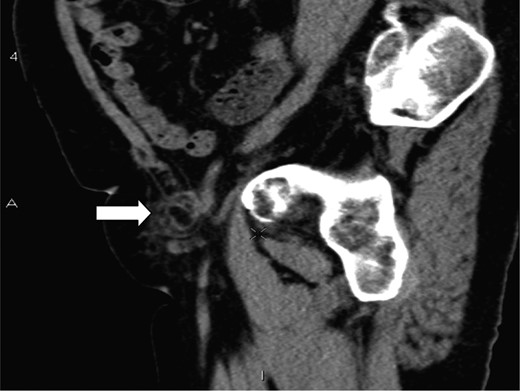

A saggital section demonstrating the tip of the appendix (white arrow) within the femoral sac.

The presence of an appendix within the femoral canal can be explained by the presence of an abnormally low/large caecum which causes the appendix to have a pelvic location [4]. The CT findings in our patient show a very long appendix (10 cm) extending from an anatomically normal caecum with the tip extending through the femoral canal and explains another plausible mechanism for a de Garengeot's hernia. The aetiology of appendicitis has long been recognized as due to intraluminal obstruction either by a fecolith, worms, tumours or lymphoid hyrperplasia [7]. It is also possible that the rigid and narrow confines of the femoral canal can lead to extraluminal obstruction of the vermiform appendix and lead to ischaemia, inflammation, necrosis and subsequent perforation.